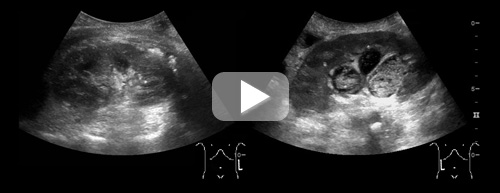

En kvinne i 80-årene ble innlagt på medisinsk avdeling på grunn av brystsmerter, feber og dyspné. Ved klinisk undersøkelse var hun øm i epigastriet og ned mot høyre flanke. Blodprøver viste leukocytter 48 mmol/l (3,5 – 8,8 mmol/l) og CRP 185 mg/l (< 5). Abdominal ultralydundersøkelse viste patologisk forstørret høyre nyre med moderat hydronefrose og dilatert ureter. Både calyces og ureter hadde småkornet hyperekkogent innhold. Funnene var forenlige med pyonefrose. Det ble anlagt et nefrostomikateter hvor det tømte seg tyktflytende illeluktende puss.

Pyonefrose er en purulent infeksjon i et obstruert nyrebekken. Pasientene har ofte et septisk bilde med høy feber, frysninger og flankesmerter. Ultralydmessig fremstår pyonefrose som en hydronefrotisk nyre med ekkogent innhold i samlesystemet. Ofte vil man kunne se et debris-væskespeil som beveger seg når pasienten endrer leie. Pyonefrose er en urologisk akuttilstand som krever intravenøs antibiotikabehandling og anleggelse av nefrostomikateter for avlastning og drenasje.

På figuren ser man pasientens normale venstre nyre til venstre. Til høyre ser man den hydronefrotiske høyre nyren med tydelig ekkogent innhold. Se video på nett for fremstilling av hele nyren, der man også kan se proksimal pyoureter.